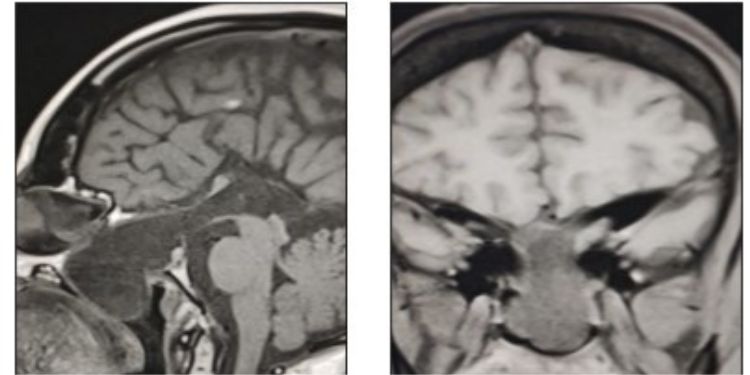

A Treatable Cause of Progressive Visual Loss

Authors: Susan Abraham Miny, Gladson Nikhil

Published on 18 Dec 2023